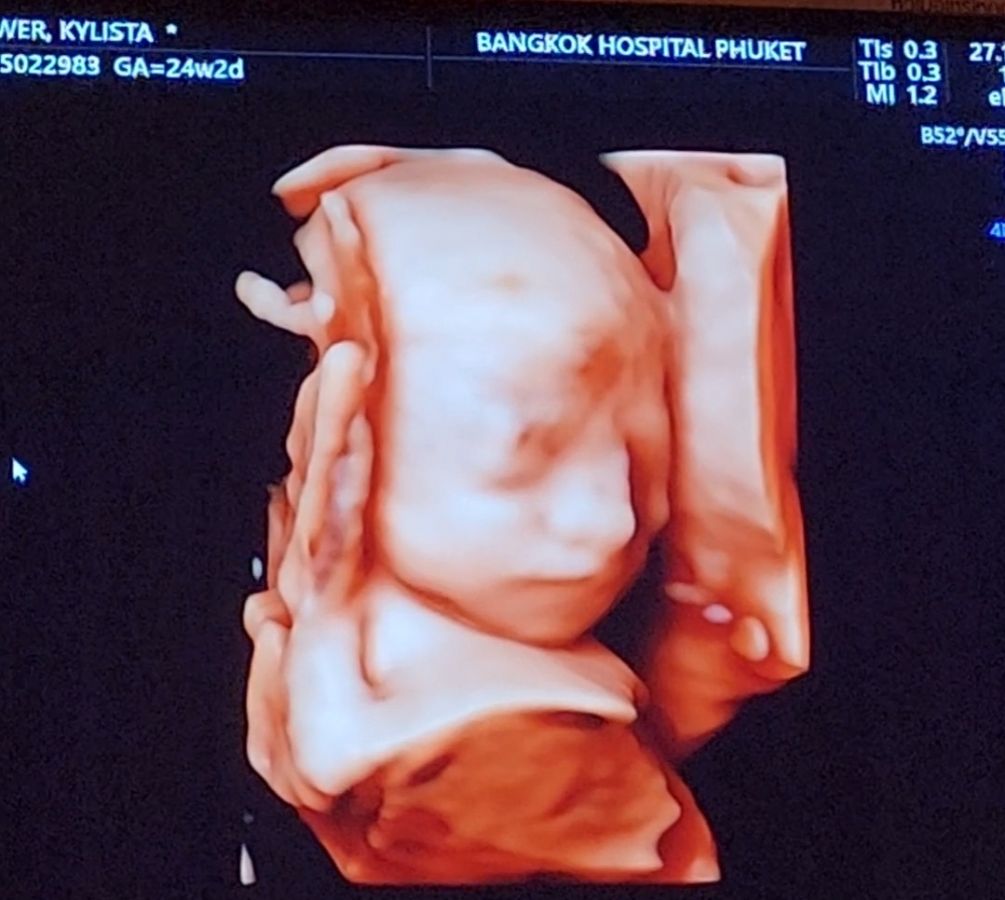

Hello, my name is Zach. My wife, Kylista, and I are expecting our first child—a baby girl—this April. Her name is Elliora Roos Foose, and she is already so deeply loved.

A few weeks ago, our world shifted. During a routine prenatal check-up, Elliora was diagnosed with a rare congenital condition called Duodenal Atresia. This means that the first part of her small intestine is blocked, preventing food and fluids from passing from her stomach into the rest of her body. Because of this, Elliora will need specialized surgery the day after she is born, followed by delicate and extended care in the Neonatal Intensive Care Unit (NICU).